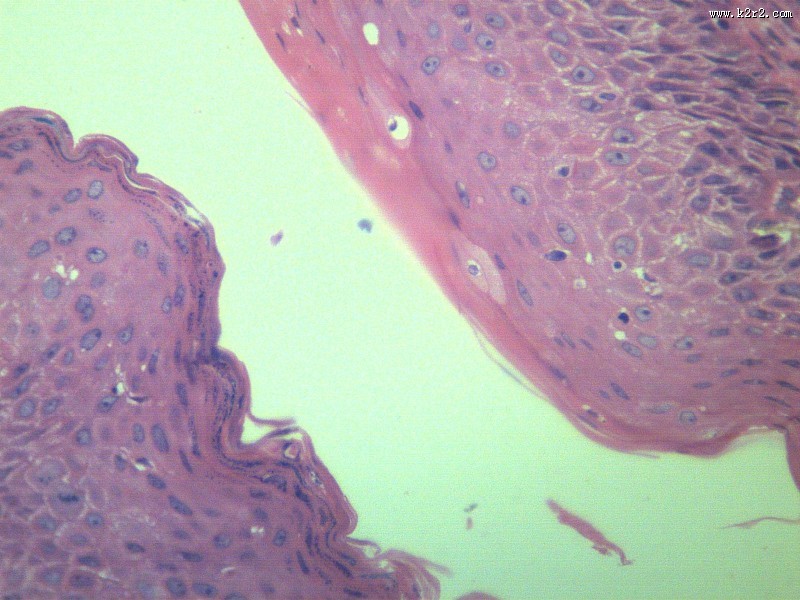

乳头状瘤 - 第10张

乳头状瘤

图集中 / 共有 12 张图片

papilloma of papilla